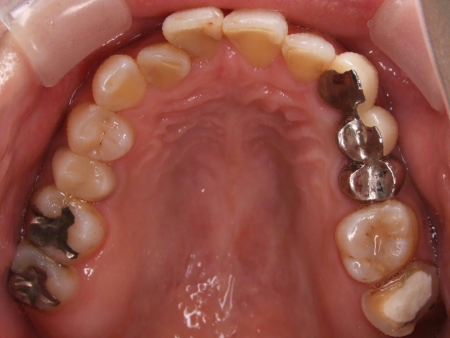

拝見したところ、歯と歯が並ぶ土台の骨「歯槽基底」の大きさの不調和により歯並びがガタガタになる「叢生(そうせい)」が全体的に生じており、また上下の前歯の重なりが深いため下の歯が見えない「過蓋咬合(かがいこうごう)」も認められました。

下の奥歯5本(右第2小臼歯/5番、左右第1大臼歯/6番、左右第2大臼歯/7番)が欠損したまま長く放置されていたことが原因で、噛み合う歯がなかった左上の奥歯(第1大臼歯)は本来の位置より下に伸びる「挺出(ていしゅつ)」が起き、左下の歯2本(第1小臼歯/4番、第2小臼歯)も内側に倒れたことで、下前歯の叢生が悪化したと考えられます。

さらに左上の歯(第1小臼歯)の欠損部位は両隣の歯2本(犬歯/3番、第2小臼歯)を土台に人工歯を橋渡しにする被せ物「ブリッジ」が装着されており、お口を開けたときに銀歯が目立つことに加えて、歯の色が全体的に黄ばんでいるため見た目が良くない状態でした。

下の奥歯4本(右第2小臼歯、左第1大臼歯、左右第2大臼歯)には、シミュレーションで決定した位置に正確にインプラントを埋入しました。

次に、左上のブリッジの土台歯だった2本(犬歯、第2小臼歯)とインプラントを埋め込んだ4本それぞれに仮歯を装着したあと、上下すべての歯の表側に矯正装置を装着します。